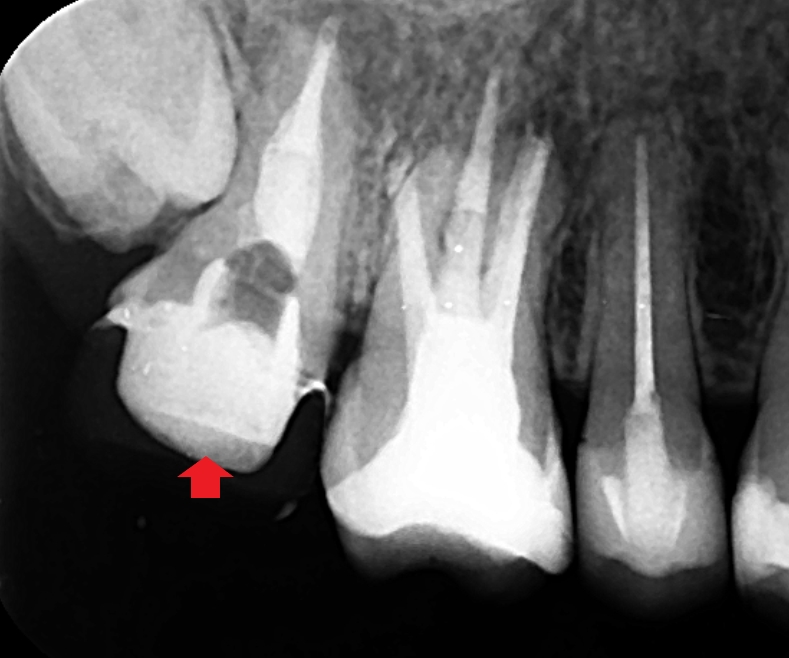

精密根管治療により、膿の改善を図りました。上の画像は根管充填時のレントゲン写真です。